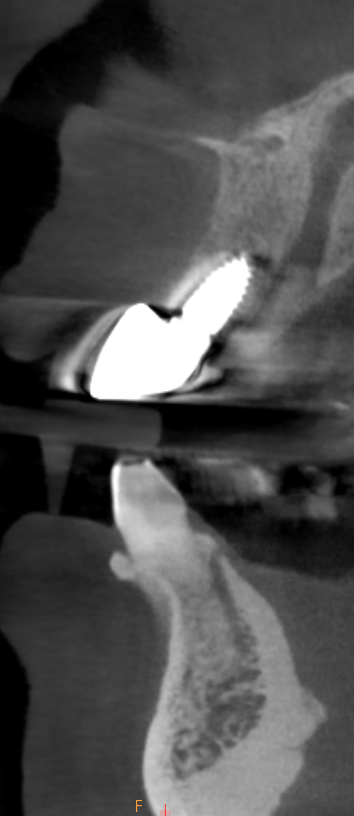

右上ソケットリフト併用インプラント

インプラント埋入後CT画像

埋入前CT画像

| 患者情報 | 50代女性 |

|---|---|

| 治療期間 | 約8カ月 |

| 治療費 | 1.045.000円(税込) |

| 治療内容 | 右上はソケットリフトと同時にインプラント埋入を行っています。左下はインプラントを通常埋入しています。 |

| リスクと副作用 | 外科手術により、術後数日間、腫脹や疼痛を伴うことがある。 |